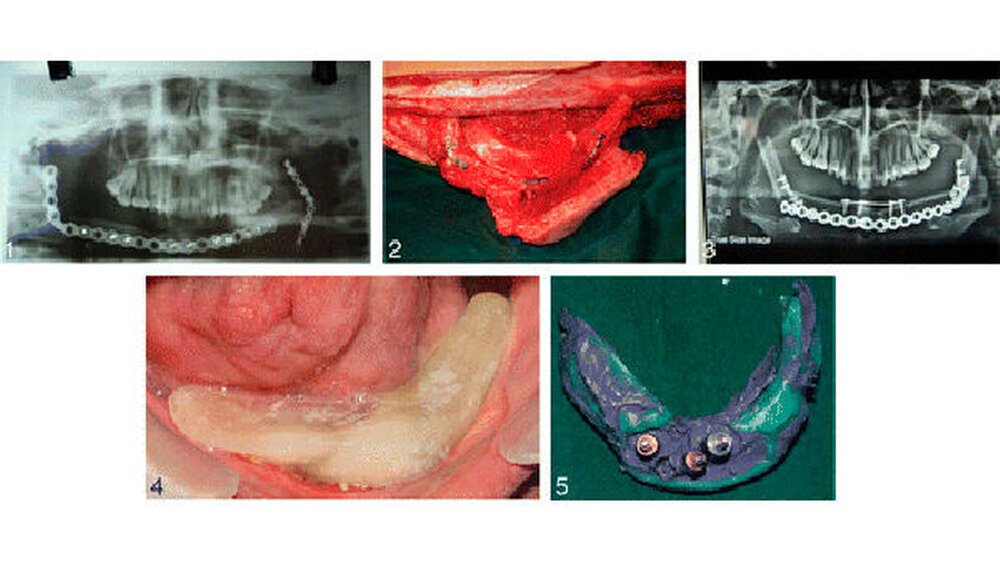

Der Fall:In diesem Fallbericht geht es um eine 24-jährige Frau. Eine Geschwulst in ihrem Kiefer war drei Jahre zuvor entfernt und der Kiefer mit Material aus einem ihrer Wadenbeinknochen wiederaufgebaut worden - ohne Erfolg. In einer zweiten OP wurde der Eingriff wiederholt. Zusätzlich wurden vier Implantate inseriert und eine Zahnprothese eingefügt.